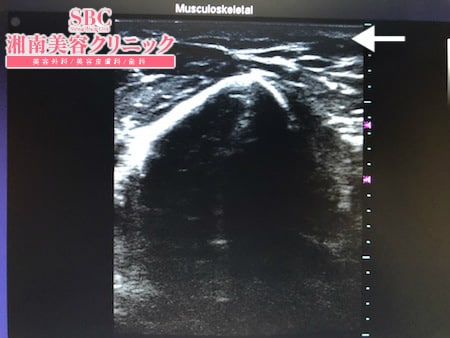

No.239542【脂肪吸引】【動画あり】湘南美容外科脂肪吸引最高責任者である竹田先生による脂肪吸引のフォトギャラリー!他院の再手術!ダイエットしても二の腕だけは細くならないので脂肪吸引する!術中3Dタッチビュー・左ちからこぶ ?

今回はその術中変化を紹介しましょう。